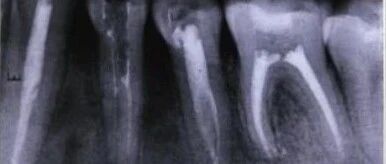

Case Study of C-shaped Root Canal Treatment for the First and Second Premolars in the Left Mandible

Case provided by:Associate Chief Physician Ye Weihua, Tongji Hospital, Tongji Medical College, Huazhong University of Science and Technology 【Patient Basic Information】: Male, 17 years old Main Complaint: Post-operative recovery from left mandible cyst curettage for over 2 months Present Illness: The patient was admitted to our hospital’s oral and maxillofacial surgery ward 2 months ago … Read more